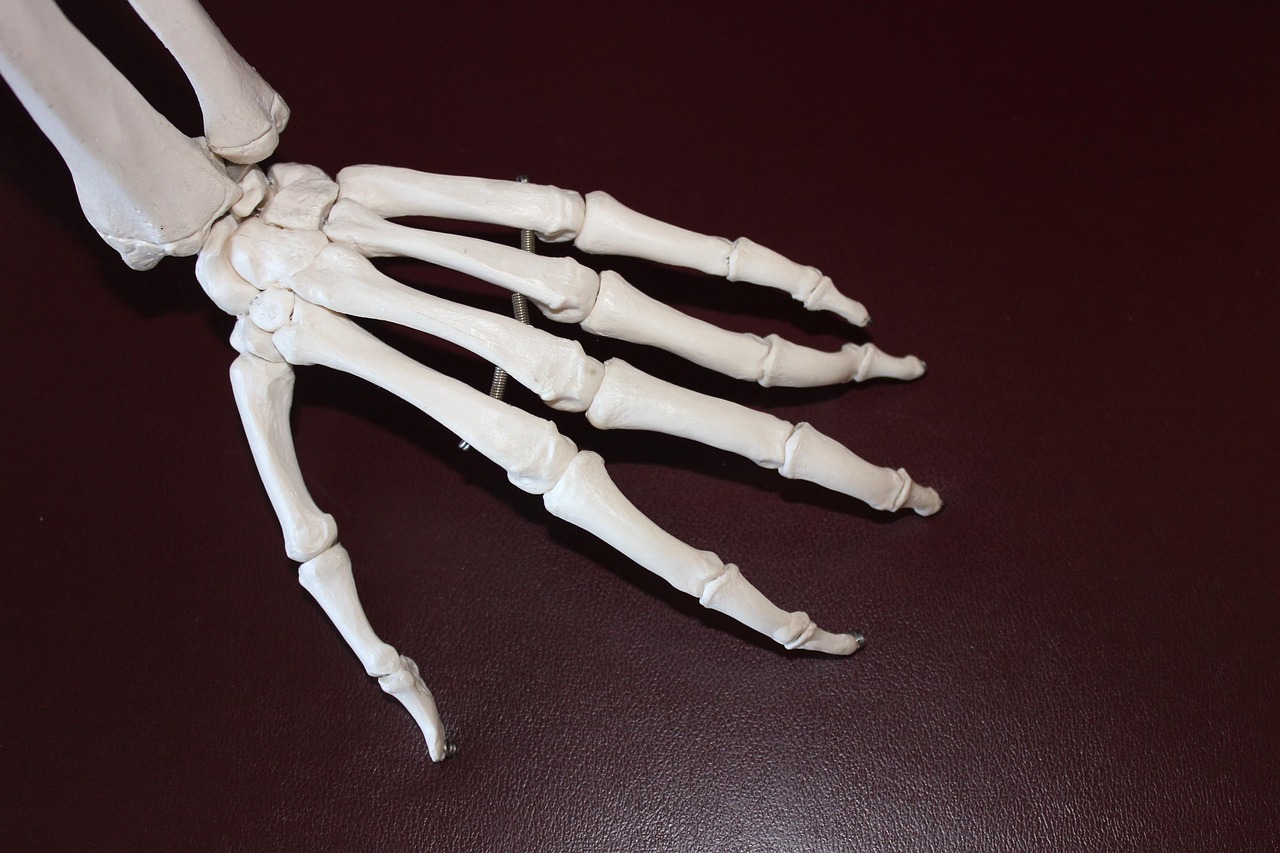

O hábito de estalar os dedos pode causar artrite? Veja se é mito ou verdade